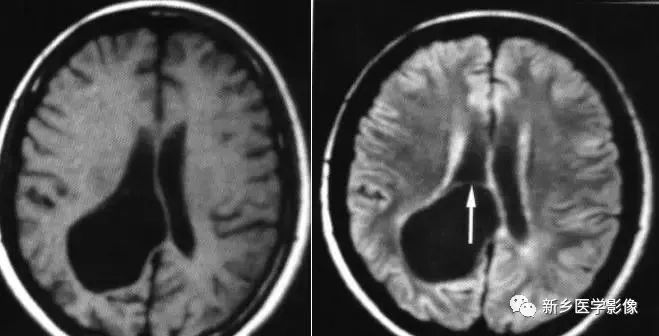

(2)脑裂畸形:胚胎期脑的发育经历6个主要阶段:①背侧诱导阶段;③腹侧诱导阶段;③神经增生阶段;④神经元移行阶段;⑤组织形成阶段;⑥髓鞘形成阶段。脑裂畸形发生在神经元移行阶段。脑裂畸形可累及一侧或双侧大脑半球,脑裂畸形位于侧面.常累及中央前、后回区偶尔位于大脑半球的其他部位。脑裂畸形的裂隙可以很窄,裂隙两侧灰质紧密相贴,称闭合型。裂隙也可以很宽,中间为脑脊液,分离型。

分离型脑裂畸形需要与脑穿通畸形囊肿鉴别.脑裂畸形的裂隙两旁一定为一灰质结构,而脑穿通畸形囊肿周围无脑灰质包绕。裂隙两旁是否为灰质结构是区别脑裂畸形与脑穿通畸形囊肿的可靠征象。裂隙两侧的灰质可不正常,可呈多小脑回样。脑裂畸形也可合并脑灰质异位。

分离型在CT很容易显示.闭合型有时容易漏诊.MRI对裂隙两侧的灰质结构容易辨认。脑裂畸形常合并透明隔缺如.侧脑室扩大,脑裂畸形处脑室边缘不规则.常可见指向裂隙的裂或 三角形憩室存在。

临床上脑裂畸形常表现有癫痫发作,其他神经系统症状可从很轻微到很严重.主要取决于脑裂畸形使脑组织缺损的严重程度。单侧闭合型脑裂畸形症状通常较轻,双侧分离型脑裂畸形症状较明显。